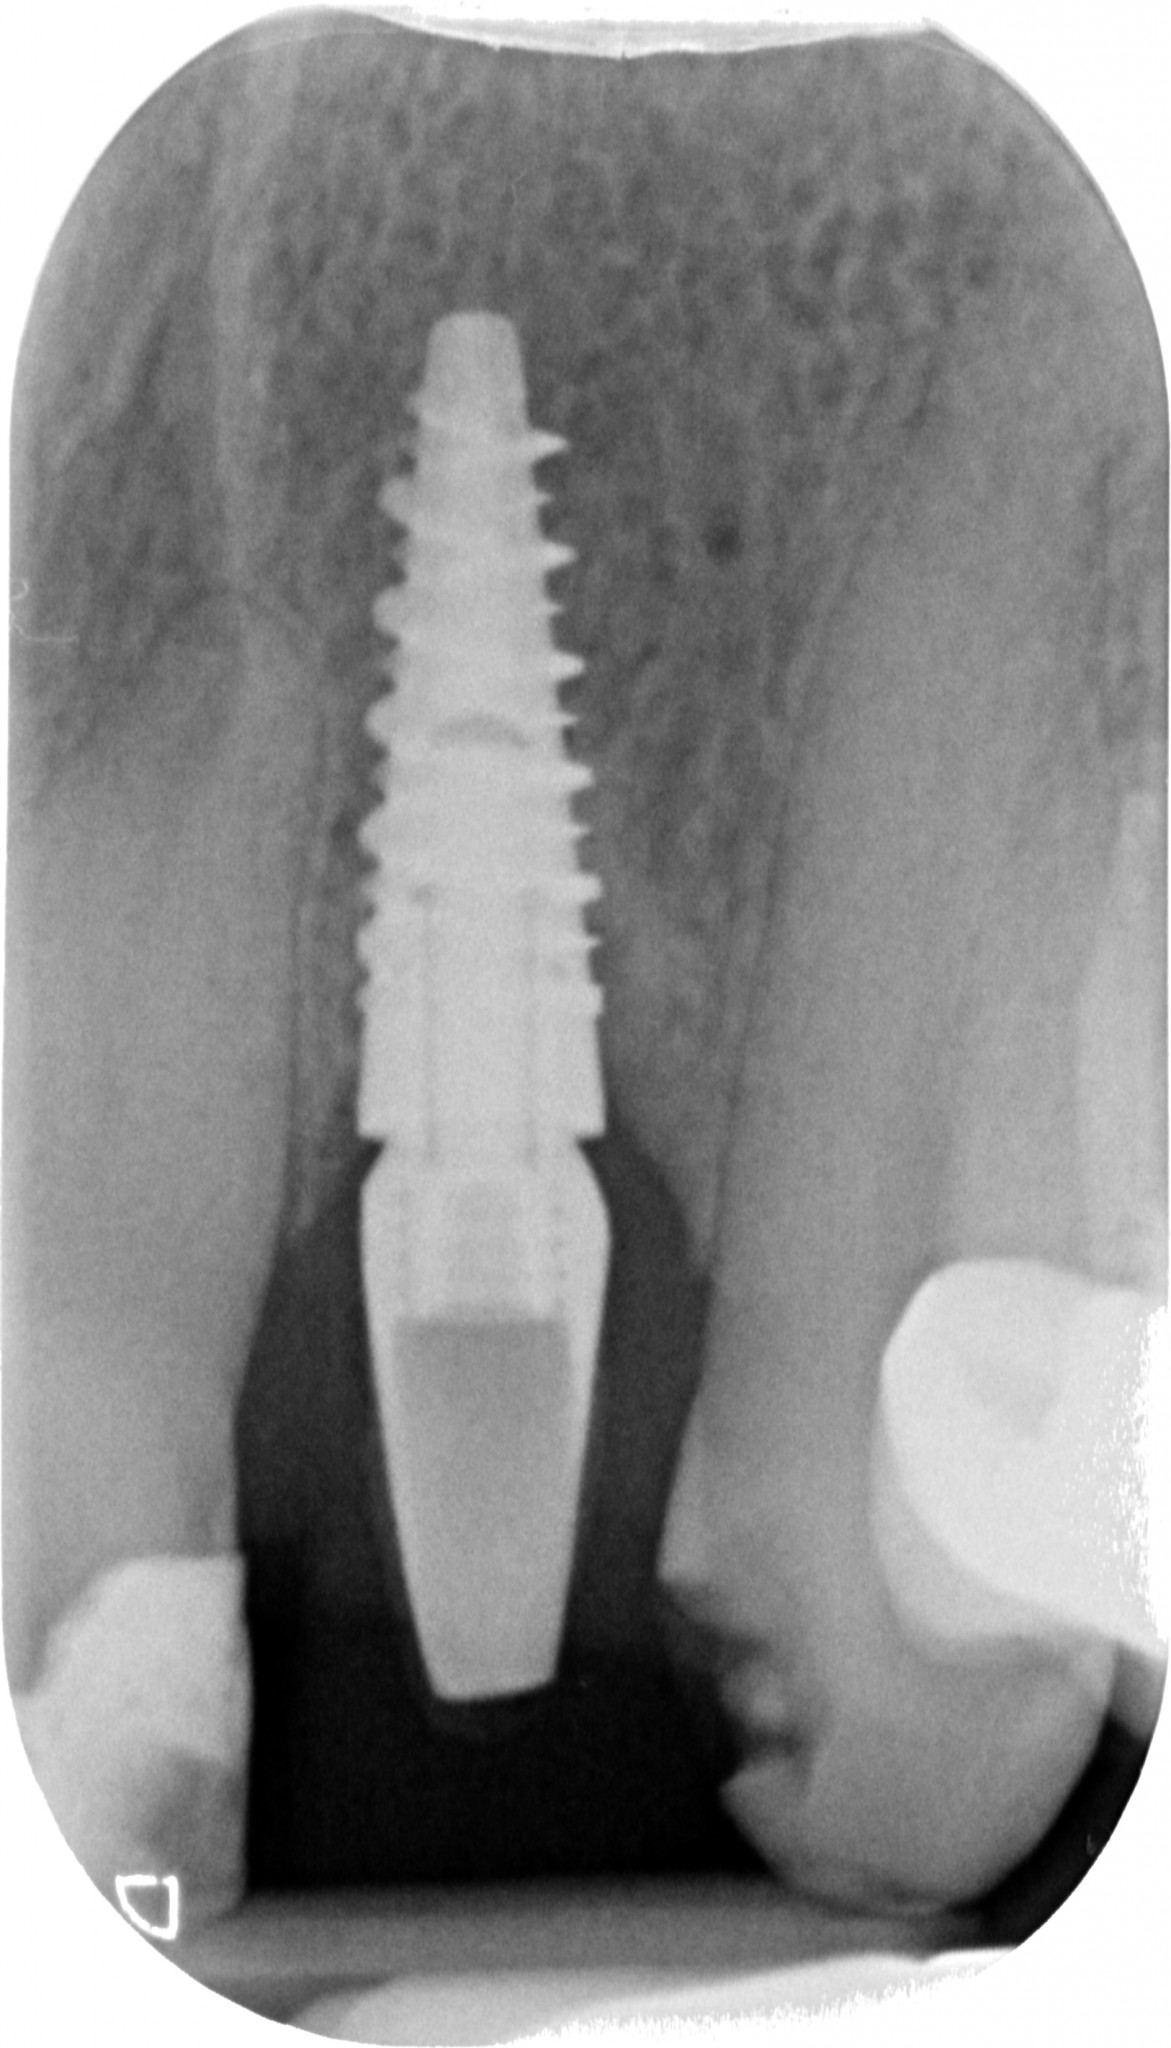

“Guarda questa lastra, cosa ne dici? Sta bene questo impianto?”

PERFETTO direi io, neanche un po’ di riassorbimento. Credo che tu sia d’accordo con me.

Ma torniamo alla fistola di Rosetta. I tessuti molli non devono essere rispettati e gestiti solo in fase chirurgica ma anche in fase protesica. Se il tuo rispetto della biologia è quello che vedi qua sotto, una fistola sarà la cosa meno grave che ti potrà capitare.

Osserva:

- La rifinitura del moncone.

- La pulizia del moncone nella zona a stretto contatto con l’osso.

- La precisione del provvisorio.

- L’invasione dei tessuti da parte del margine di preparazione con impossibilità assoluta di gestire l’interfaccia di cementazione.